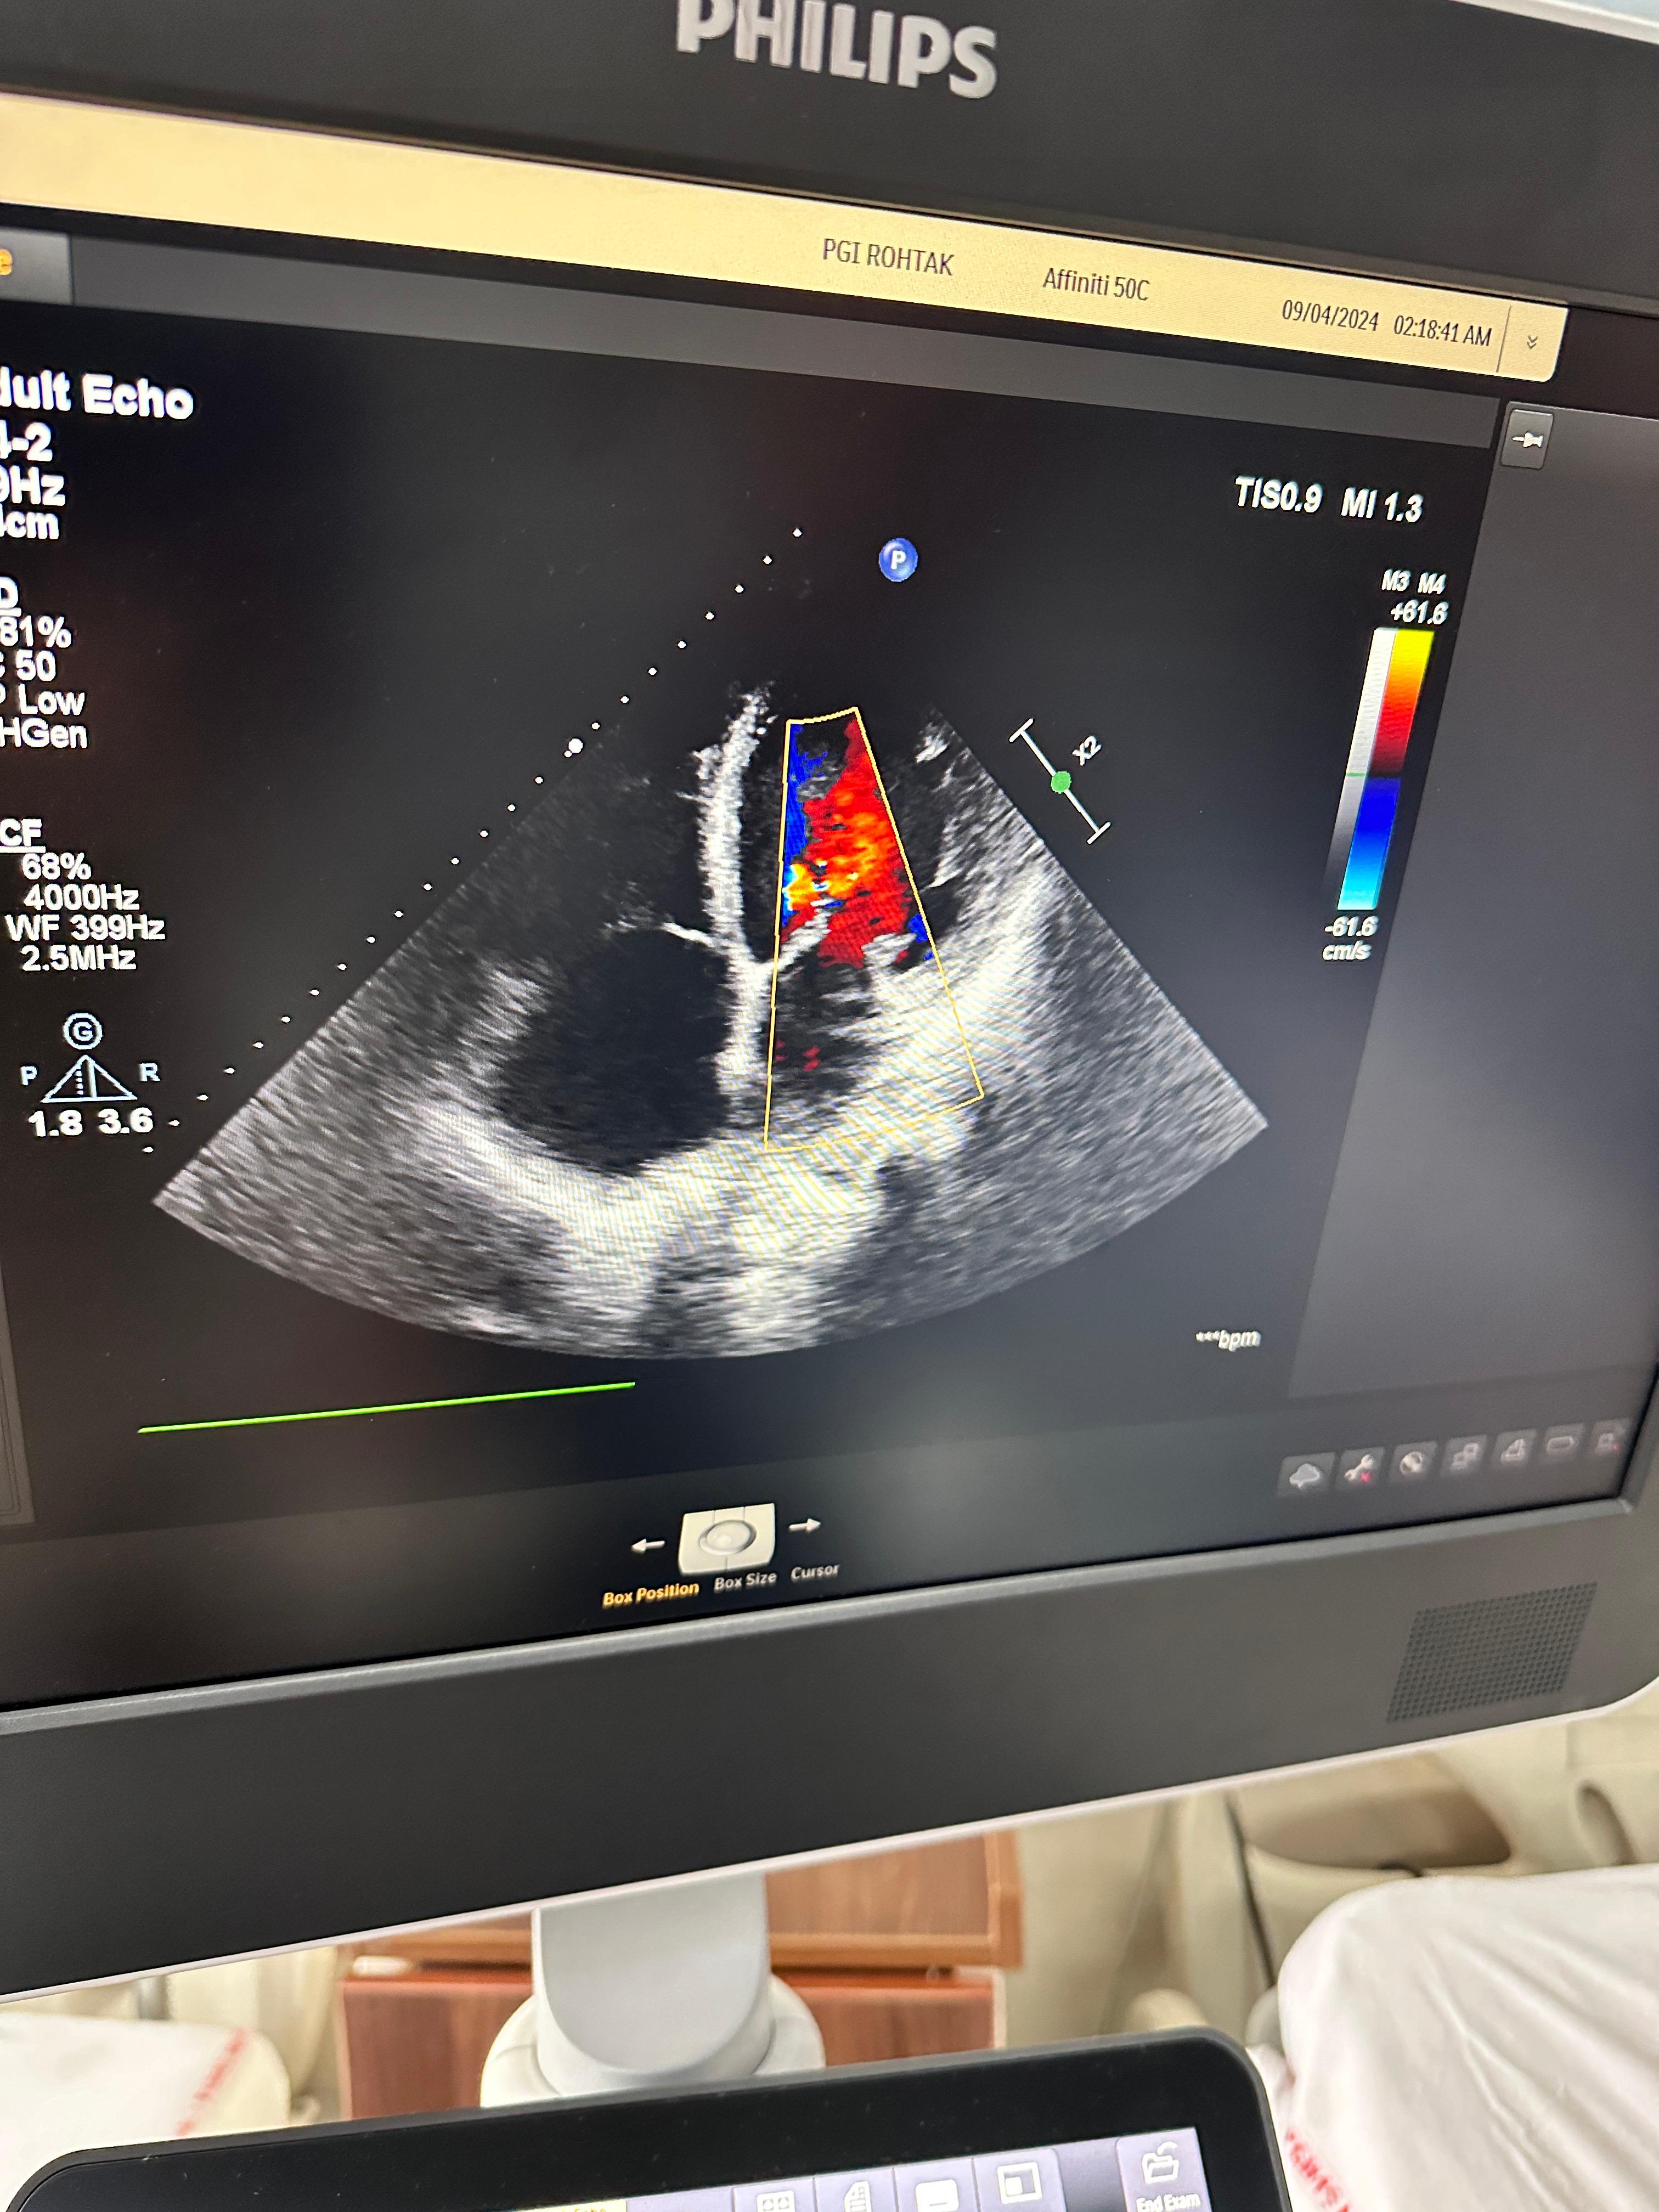

Transthoracic ECHO (TTE)

Transthoracic Echocardiography (TTE) is one of the most common heart imaging tests. It uses ultrasound waves to create real-time pictures of the heart. This painless, non-invasive test helps doctors evaluate heart structure and function quickly.

TTE is an ultrasound-based diagnostic test. A small device called a transducer is placed on the chest. It sends sound waves that bounce off the heart and create images. These images allow cardiologists to examine heart chambers, valves, and blood flow.